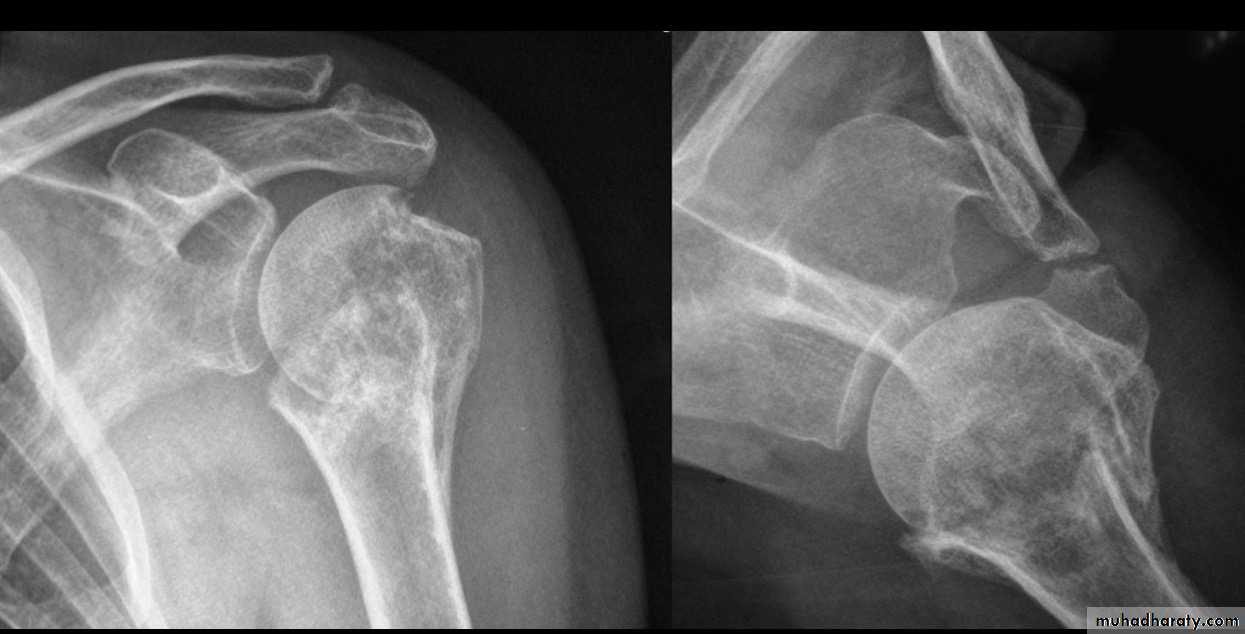

FOUR PART FRACTURE

32

X RAY

33

CT

TRATMENT IN YOUNG

35